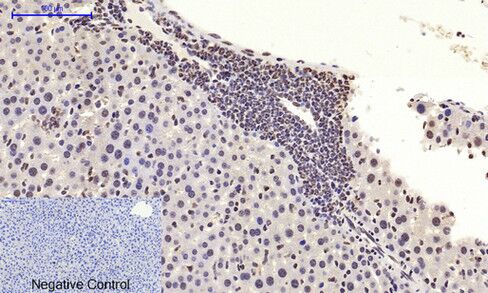

Immunohistochemical analysis of paraffin-embedded RAT testis tissue using c-Myc Polyclonal Antibody.